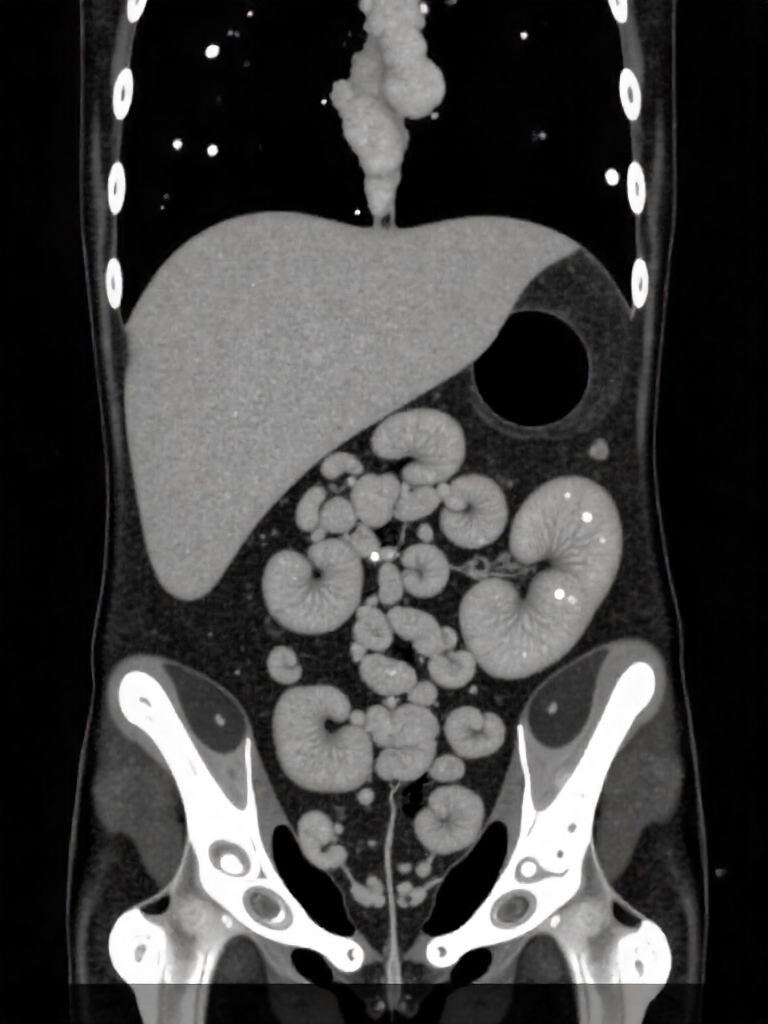

Fat distribution, particularly visceral fat stored around organs or within the liver and pancreas, can lead to insulin resistance or impaired insulin secretion, even in individuals with a normal BMI. Studies utilizing imaging techniques (CT scans) have shown that individuals classified as “lean” with type 2 diabetes often exhibit abdominal fat patterns comparable to those in overweight individuals, such as increased visceral fat, altered muscle fat content, or pancreatic fat accumulation.